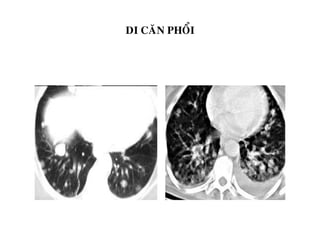

DI CAÊN PHOÅI

SOLITARY METASTASES MULTIPLE NODULES

Colon (30-40%)

Sarcomas, particularly from bone

Kidney

Testicle

Breast

Malignant melanoma

Thyroid

Sarcoma of bone

LYMPHANGITIC SPREAD CAVITARY METS

Lesions arise around chest

Simulate CHF

Lung

Larynx

Stomach

Pancreas

Cervix

Usually thick walled with nodular inner margin

Squamous cell primaries such as

Head and neck tumors

Ca of the cervix

Transitional cell ca

Melanoma

Adenocarcinoma